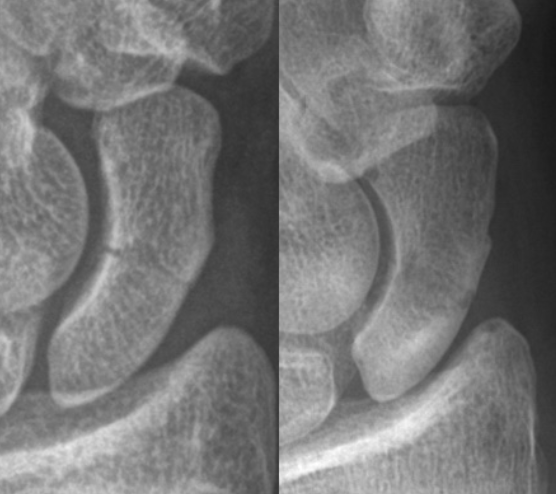

- 먼저 방사선 손목 사진을 찍어서 확인합니다. 그러나, 처음 방사선사진에서 나타나지 않더라도 골절이 의심되면 2-3주 후에 다시 찍어 재확인하여야 합니다. 필요한 경우에는 뼈스캔(bone scan), CT, MRI 등의 특수 검사를 하여 확인해야 합니다.

- 잘 확인이 되지 않았을 때 엑스레이를 반복했을 때 골절부위가 벌어진 타이밍에 관찰될 수 있기 때문입니다.

- 아래 엑스레이처럼 잘 관찰해야 보입니다.